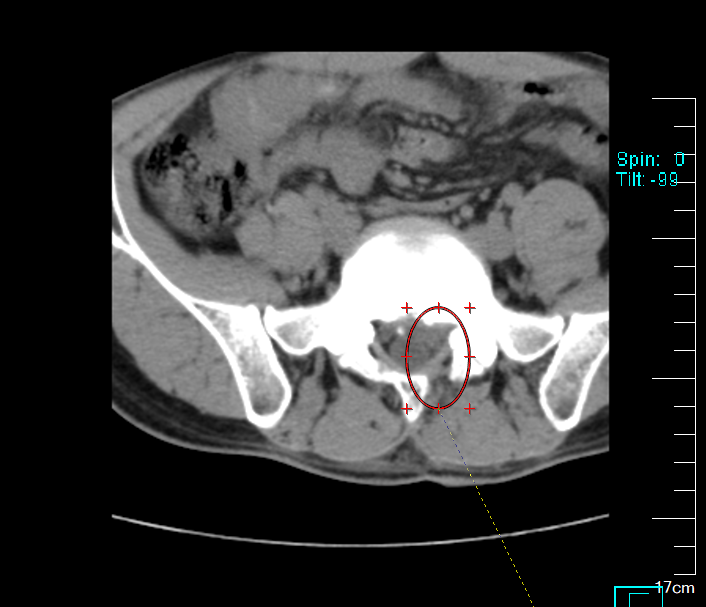

術后